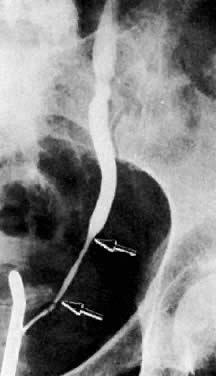

Blocking ureterogram shows narrowed area in left distal ureter ( between arrows) in a patient wtih endometrial carcinoma.

Excretory urogram shows dilated right collecting system to the ureterovesical junction in a patient with cervical carcinoma.